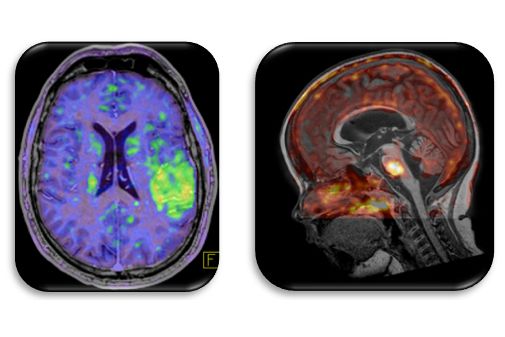

Figure: Personalized medicine through HYBRID: Patients with suspected disease undergo standardized examination protocols for the collection of biomarker information (image and non-image based information). Data are processed and interpreted prior to making a diagnosis. Decision models are supported by machine learning algorithms. In addition, diagnostic and complementary information is pooled and used for a population-based analysis and subsequent pre-selection of clinical patients for individual imaging and/or therapy options. HYBRID’s entangled research-based work packages, WP1-3, cover novel aspects of data collection, data processing and clinical translation.